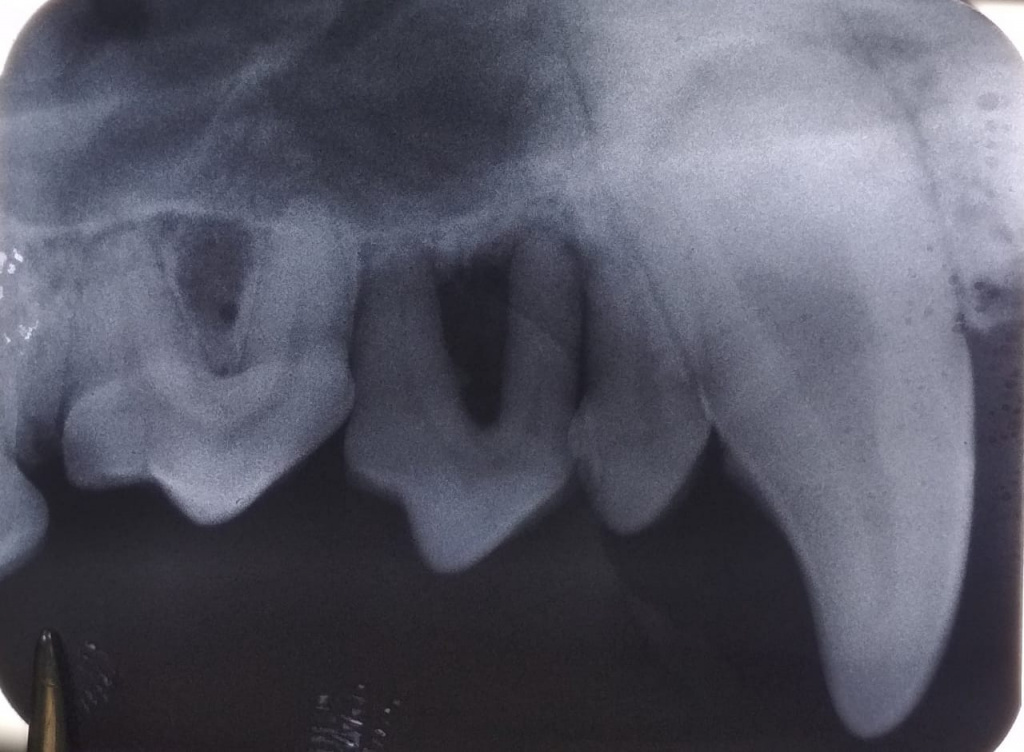

3. Далее выполняется интраоральная рентгенография, необходимая для оценки состояния корней, костных структур, периодонтальной связки и т.д.